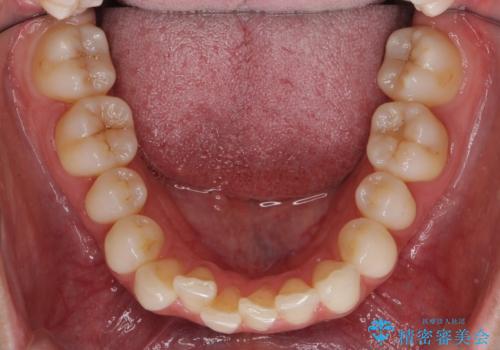

特に下の前歯のがたつきを気にされていました。

再度の後戻りを防ぐため、下顎前歯の裏にはワイヤーを貼る保定を行っています。